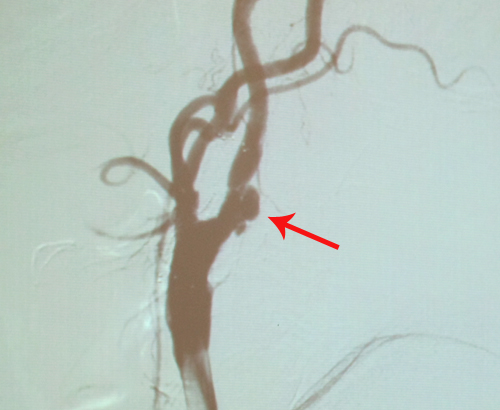

右侧颈内动脉溃疡性斑块狭窄

左颈内动脉支架植入术后

患者中老年男性,动脉粥样硬化性危险因素较多,累及冠脉、颈动脉及双下肢动脉,病变程度较重,但患者目前无TIA 及脑卒中症状。右颈内动脉狭窄尚未达70%,但斑块内溃疡,属不稳定斑块,且狭窄已>50%,产生同侧脑卒中风险较大,因此有进一步治疗指征。因对于溃疡斑块,CAS疗效不如CEA,因此CEA相对适合。患者合并有冠脉三支病变,预防围手术期心肌梗塞是关键。

2010年12月6日,协作组张勤奕教授和王冬青教授在西安交大第一医院为其顺利实施右侧颈内动脉内膜剥脱术。